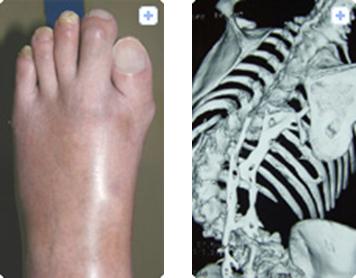

该病患者的主要症状是肌肉里会形成多余的骨组织。从孩童时期开始,患者全身肌肉包括肌肉周围的膜、肌腱以及韧带等部位逐渐变硬钙化。四肢肌肉钙化将导致手脚关节活动范围变窄以及手指弯曲,而脊椎骨钙化将导致背部变形。最终,和呼吸相关的肌肉以及口腔肌肉出现钙化骨化,导致患者进食困难和呼吸衰竭,最后在痛苦中走向死亡。

进行性肌肉骨化症,伴随的大拇指弯曲以及脊椎变形

图片来源:http://fop.umin.jp/fop.html